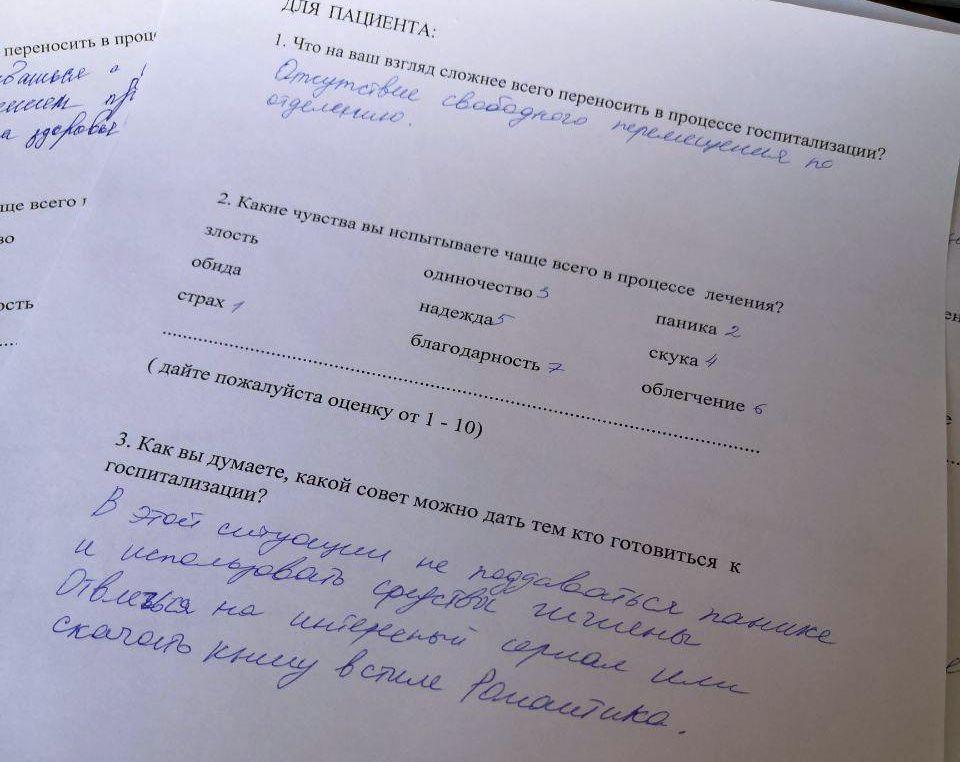

Анкетирование пациентов: почему это так важно?